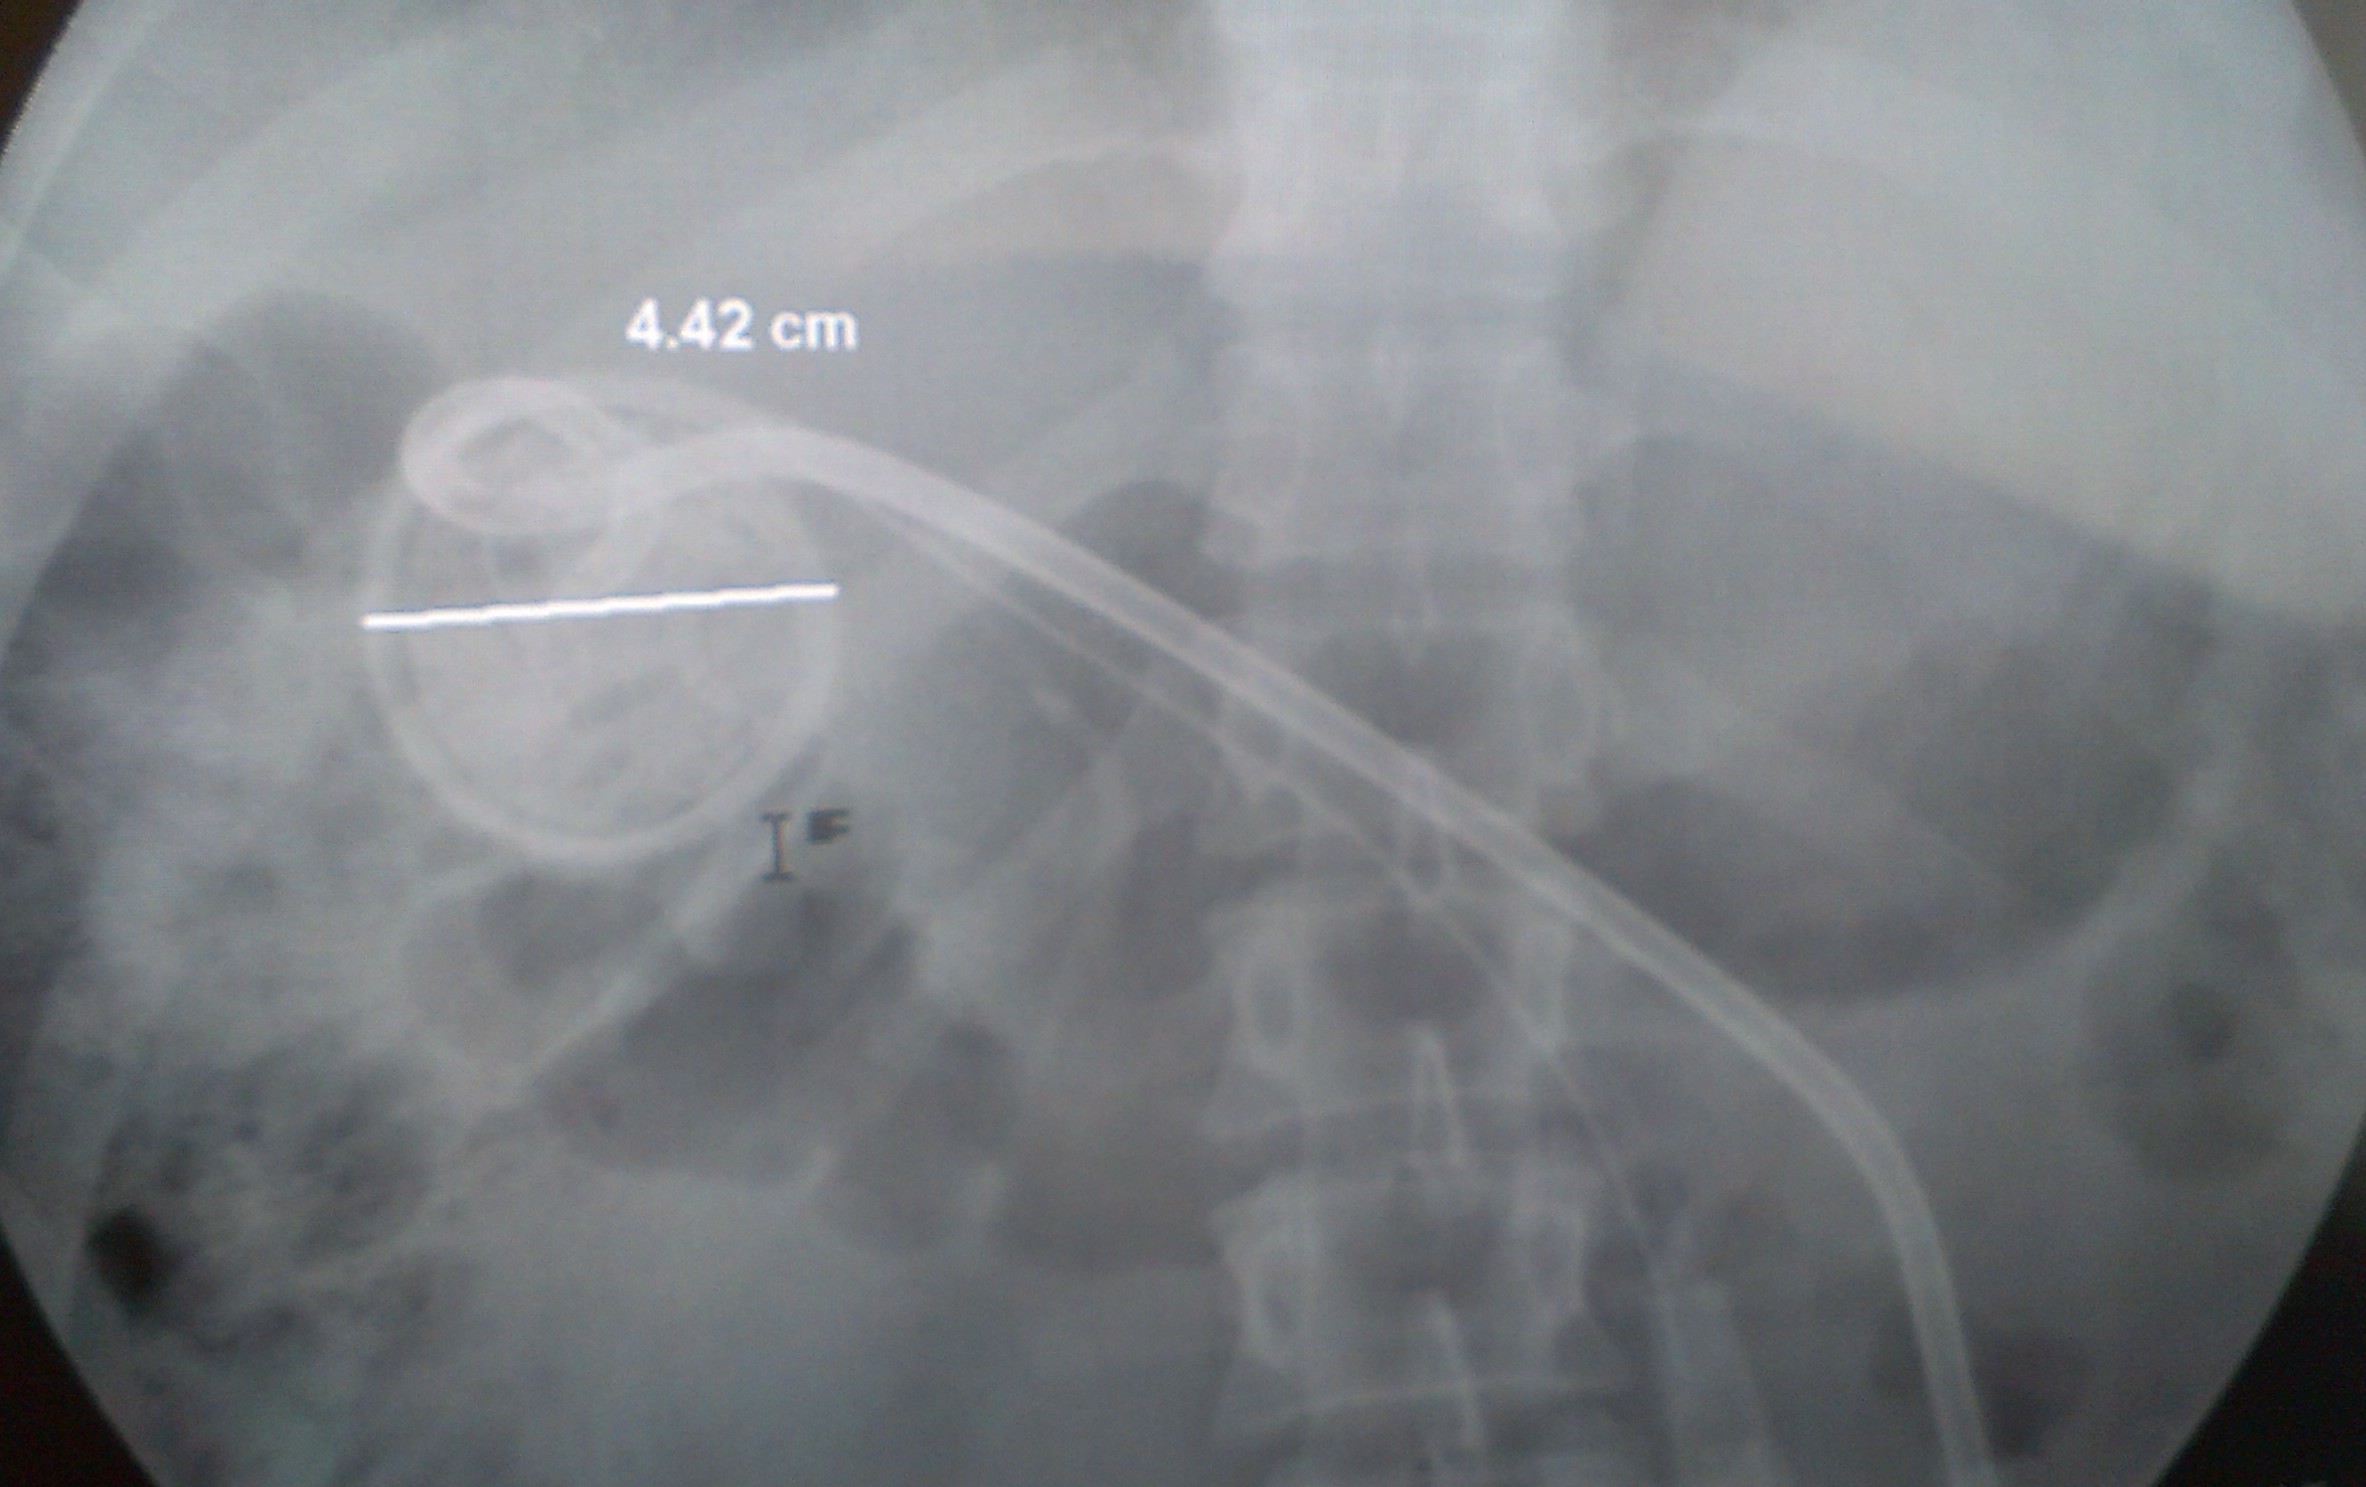

Фистулография после операции:

Киста диаметром 20 см, дренажи в верхнем полюсе кисты.

Учитывая, что размеры кисты очень большие, а доступ осуществлялся через удаленный участок печени и под острым углом, то длинны дренгажей хватило только для установки фисированного замком кольца в верхнем полюсе кисты. Тем не менее контрастирование и опорожнение полости кисты было адекватным. Попадания контраста в желчные протоки не выявлено: